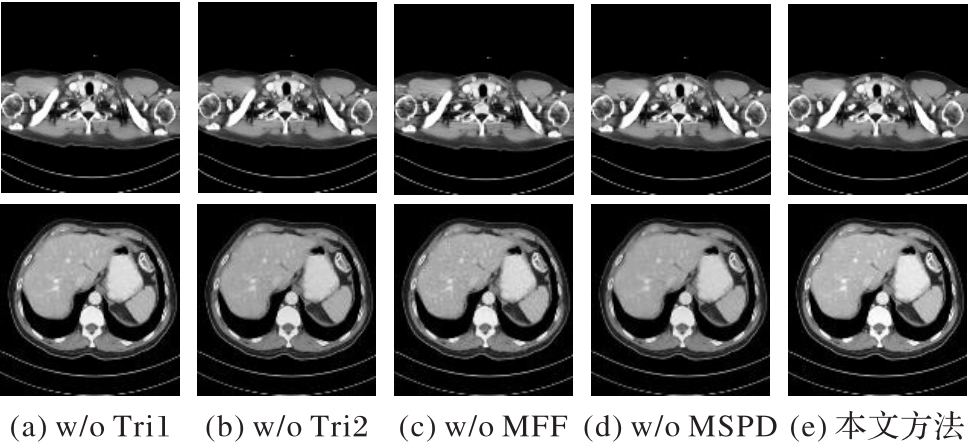

| 模型 | 子模块 | PSNR/dB | SSIM | |||

|---|---|---|---|---|---|---|

| Trident Block | SCAM | MFF | MSPD | |||

| w/o Tri1 | √ | √ | √ | 29.712 8 | 0.879 9 | |

| w/o Tri2 | √ | √ | √ | 31.052 1 | 0.867 0 | |

| w/o MFF | √ | √ | √ | 31.120 5 | 0.877 2 | |

| w/o MSPD | √ | √ | √ | 30.975 4 | 0.875 1 | |

| Trident GAN | √ | √ | √ | √ | 31.5193 | 0.8830 |

Tab. 5 Average quantified performance of ablation experiments